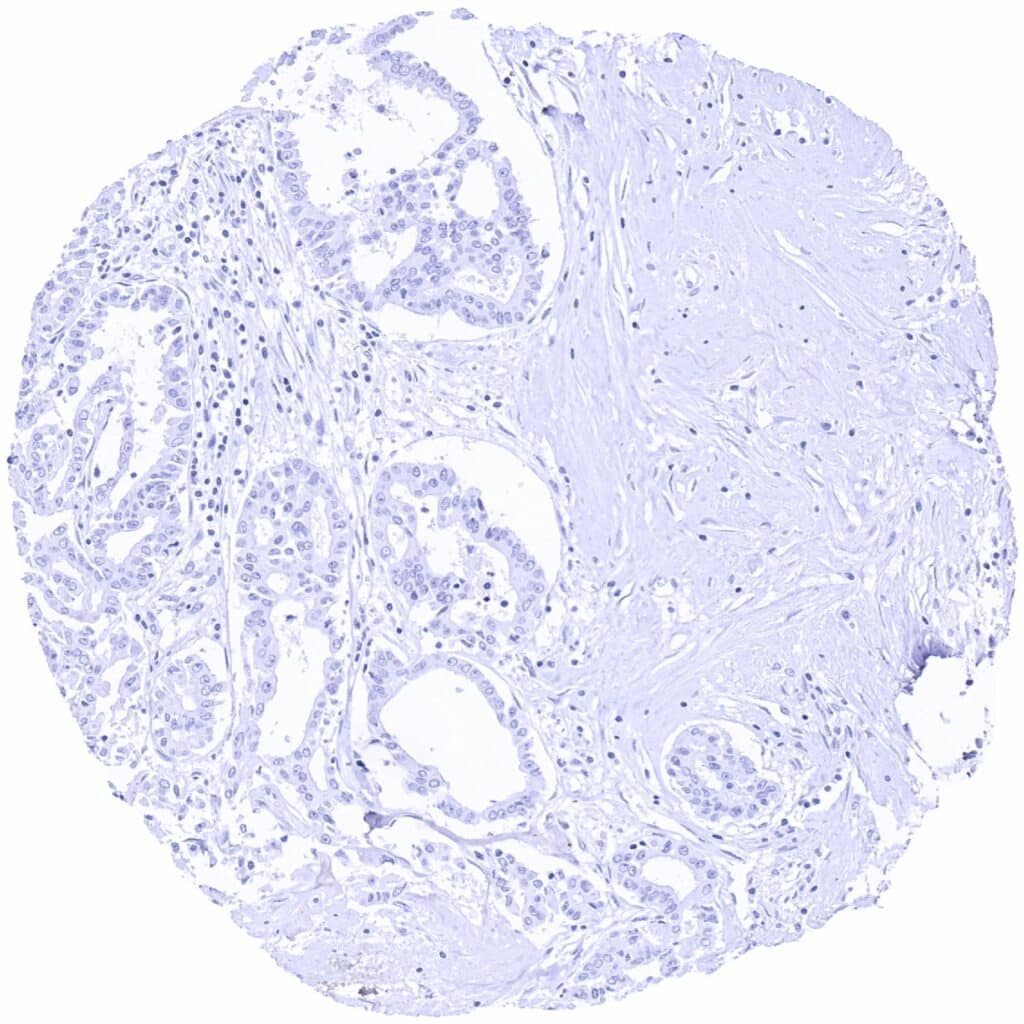

PAX6 antibody [MSVA-706M] HistoMAXTM

Breast – PAX6 negative invasive breast cancer of no special type (NST)